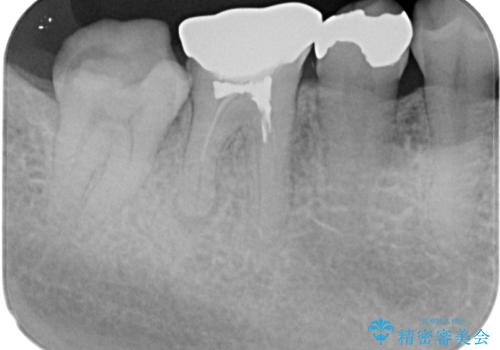

- 右下の銀歯が取れたとのことで来院された患者様です。脱離をしたメタルインレーを戻してみましたが不適合を認めました。メタルインレーの範囲が大きく、残っている歯の範囲を考慮してオールセラミッククラウンにて補綴治療を行っていくことにしました。

拡大鏡視野下で虫歯の除去を行い、オールセラミッククラウンに適した形に整えました。

精密印象時、唾液の量が多かったため個歯トレーを使用しています。